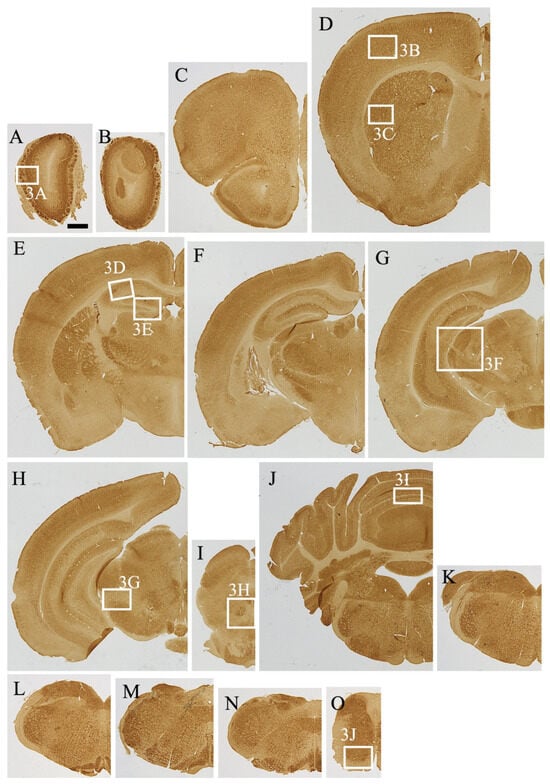

3.2. Overview of MEGF8 Distribution

3.3. Detailed Distribution of MEGF8-IR in the Mouse CNS